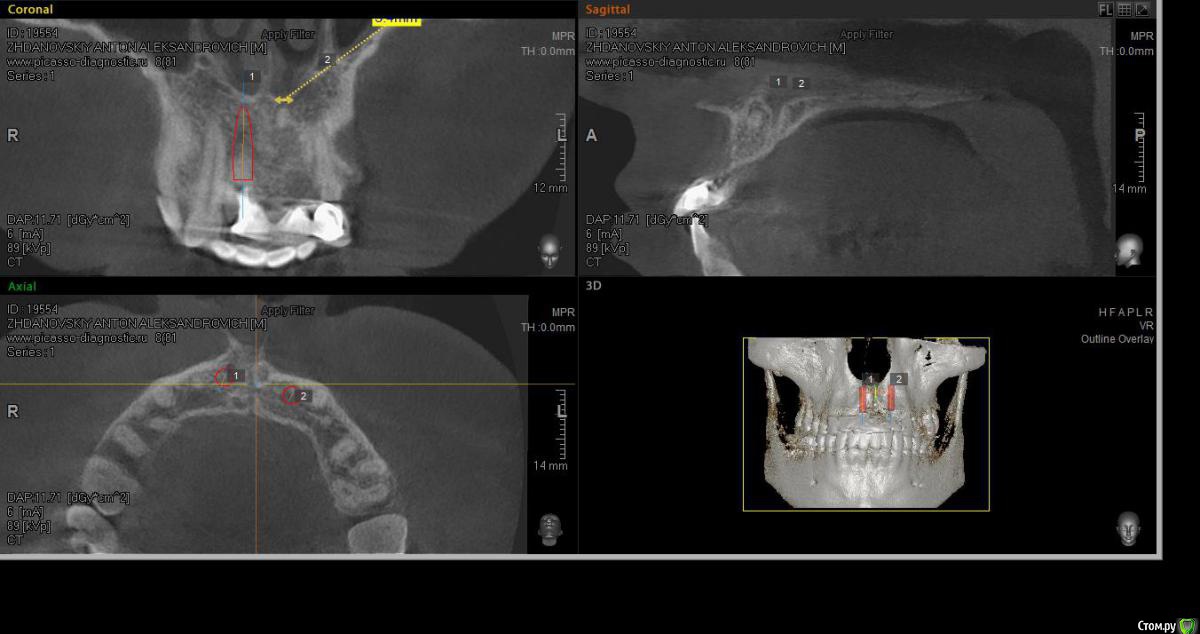

elen_only Опубликовано 1 августа, 2018 Поделиться Опубликовано 1 августа, 2018 Здравствуйте,коллеги! Помогите ,пожалуйста,неопытному имплантологу спланировать операцию. Пациент направлен ортопедом на удаление 11,22 зубов по поводу трещин корней. Биотип десны тонкий. Похоже,оставлен артефакт в области 21. Опыта одномоментной имплантации ,к сожалению, нет. Нервничаю.Хочу атравматично удалить 11,22 ,установить имплантаты с заглушками. Пациенту готовят сьемное на время. Через 4 месяца,поработать с десной. А корень попробовать достать через микроразрез,не отслаиваясь широко,такой опыт уже был. Подскажите,правильно ли я спланировала операцию? Или лучше сначала удалить корень а потом удалять зубы и имплантировать? Ссылка на комментарий

Irouil Опубликовано 1 августа, 2018 Поделиться Опубликовано 1 августа, 2018 Я тоже против съёмного, судя по Вашим срезам есть шансы на неплохой торк, так что, как по мне, мостик прямым методом. В идеале сразу трансплантат под понтик, но безопаснее и проще будет с этим поработать перед ортопедией - сможете спокойно снимать и моделировать овоид сколько душе будет угодно. В области 2.1, если пациента ничего не беспокоит, я бы не лез. Выводить на винтовую, рентген контроль имплантатов и корня раз в полгода/год Ссылка на комментарий